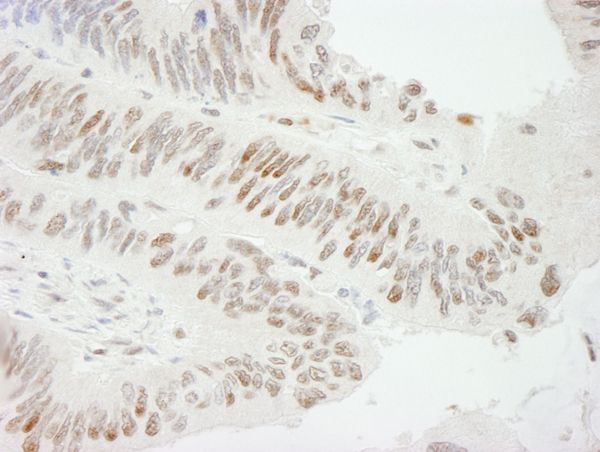

IHC (Immunohistochemistry)

(Immunohistochemistry analysis of paraffin-embedded Human colon carcinoma using ZBTB7A/FBI-1/LRF Rabbit mAb (AAA282826) at dilution of 1:100 (40x lens). Microwave antigen retrieval performed with 0.01M Tris/EDTA Buffer (pH 9.0) prior to IHC staining.)